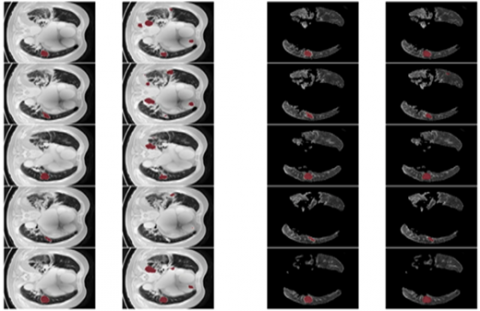

From the Table 7, it was clearly evident that our method was performed very well with few samples size from LUNA 16 dataset. The results clearly shows that out proposed model and method are good at classifying odd benign and Malignant tumours was shown in the Figure 14. As, a result the model has achieved a trust gain when compared with various others methods.

Figure 14. The proposed classifier on LuNa-16 dataset. Second column showing the original image, third column showing the lung lode, and last two is the segmented image